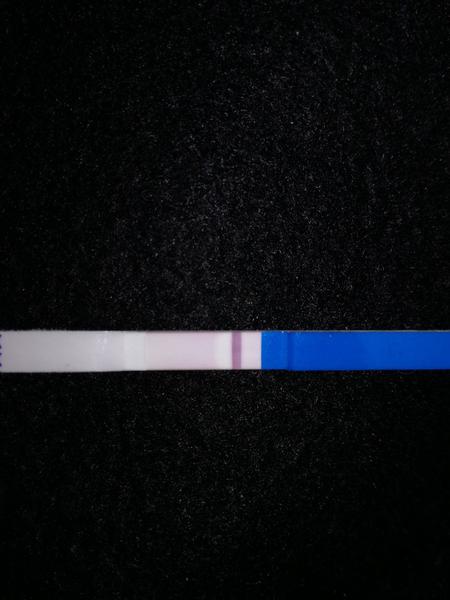

Ahojte, test je belsi, nez sneh co nam od rana pada 😕 muz mi odchadza na tri mesiace do cudziny, bol to nas posledny pokus pred cestou. Vsetkym vam prajem, nech sa vam splni vas senn, my sme sa dohodli, ze to zatial nechame tak. Drzte sa a dakujem 🏵🏵🏵